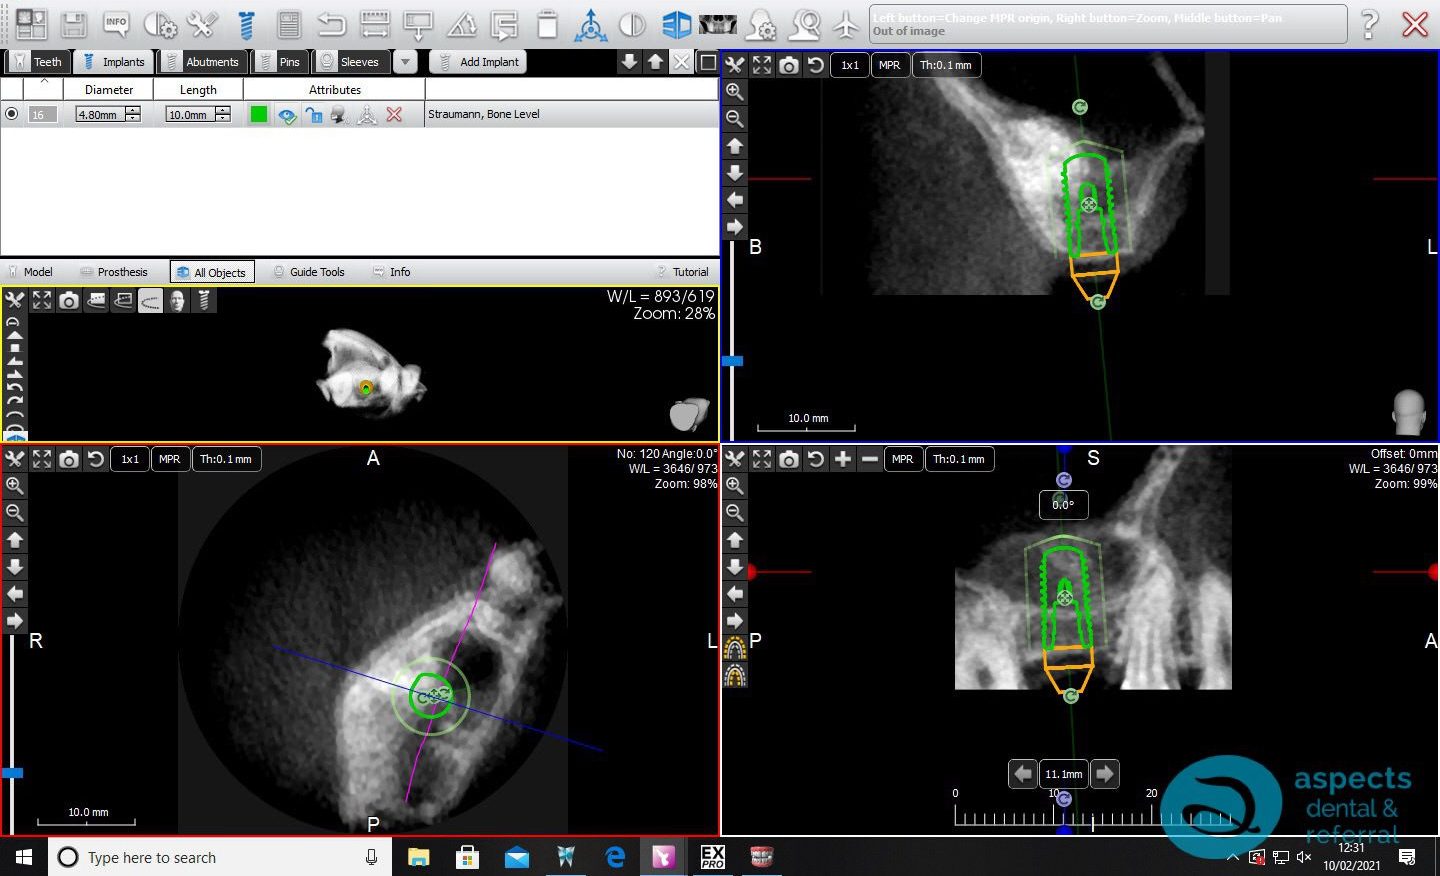

Following extraction, a sinus lift procedure was performed to augment the deficient bone volume and create adequate support for future Dental Implant Placement. After a successful healing period and radiographic confirmation of graft integration, a dental implant was placed in the augmented site.